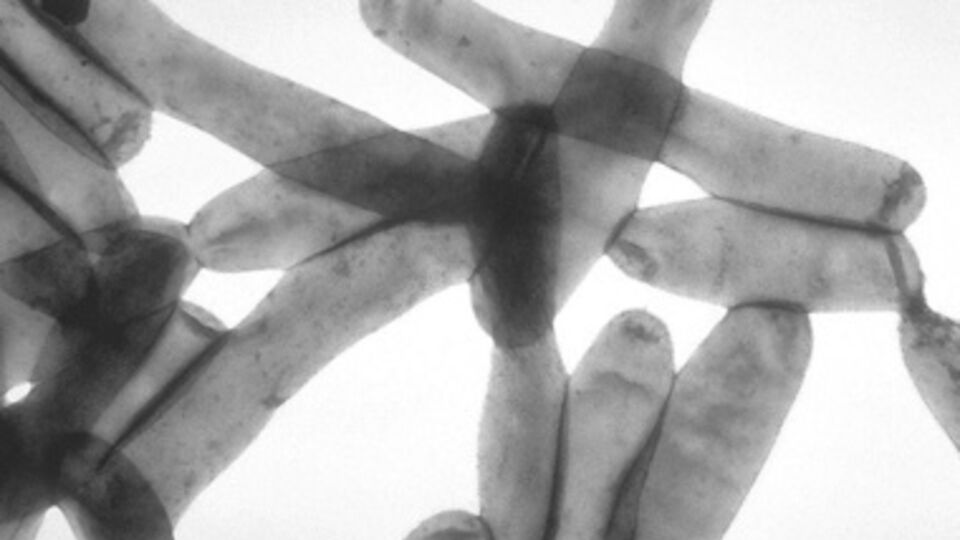

Болезнь легионеров проявляется как пневмония, обусловленная бактерией легионеллы. Болезнь легионеров обычно передается через зараженную воду. Ее бактерии могут расти в искусственных системах водоснабжения.